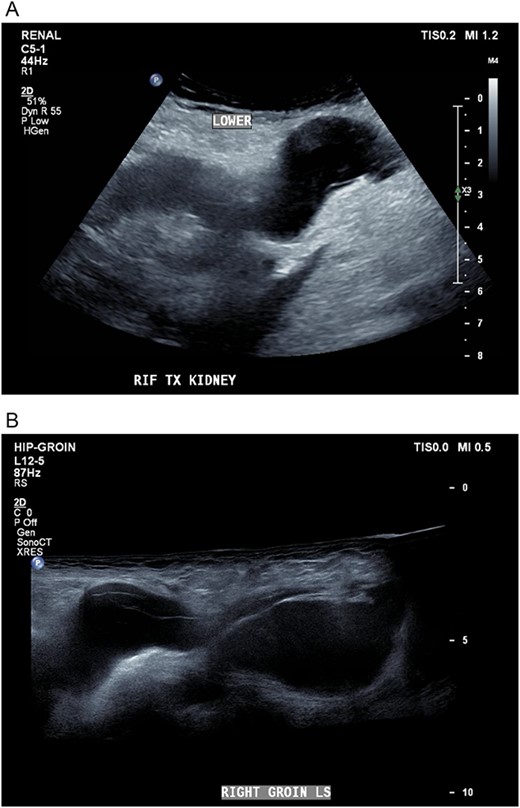

Five days later, the patient had another ultrasound and an ensuing CT KUB given recurrence of a painful groin swelling overnight. It showed a reaccumulation of the pelvic fluid collection, which extended into the groin toward the scrotum with two pockets of fluid collection measuring 4.6 × 6.5 × 2.7 cm (42 ml) and 7.7 × 3.5 × 4.6 cm (66 ml) (Figs 2 and 3). We temporized the situation by aspirating 35 ml of fluid by the bedside under ultrasound guidance for symptom relief and booked him for an elective operation given the complex anatomy of the collection.

(A, B) Targeted ultrasound showing reaccumulation of a peri-transplant collection which appeared multiloculated measuring a total of 100 ml extending into the right groin.